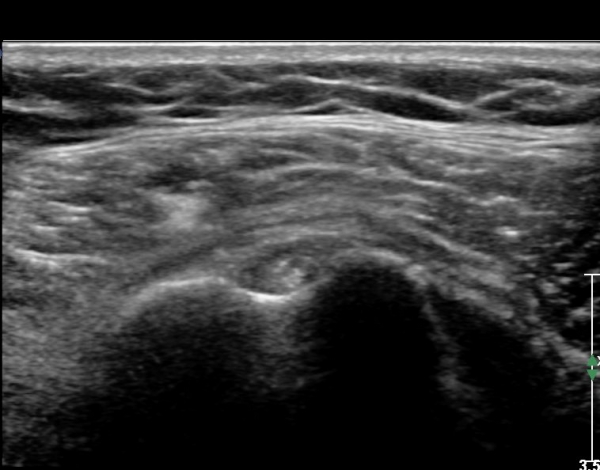

ÃÊÀ½ÆÄ ¼Ò°ß: ¿À±¸µ¹±â¿Í °ßºÀÀ» ¿¬°áÇÏ´Â ¿À±¸µ¹±â°ßº»Àδ밡 Á¤»óÀûÀÎ ¸ð½ÀÀ¸·Î °üÂûµÈ´Ù(»çÁø 1).

ŽÃËÀÚ¸¦ Á¶±Ý ¸»´ÜÀ¸·Î À̵¿ÇÏ´Ï ¿À±¸µ¹±â°ßºÀÀÎ´ë °ßºÀ ºÎÂøºÎ °ñ±ØÀÌ °üÂûµÇ°í Àδë

½ÉÃþºÎ¿¡ ¼ö¾×Àú·ù°¡ ÀÖ¾î ¸¸¼ºÀûÀÎ Ãæµ¹À» ÃßÁ¤ÇÒ ¼ö ÀÖ´Ù(»çÁø 2).